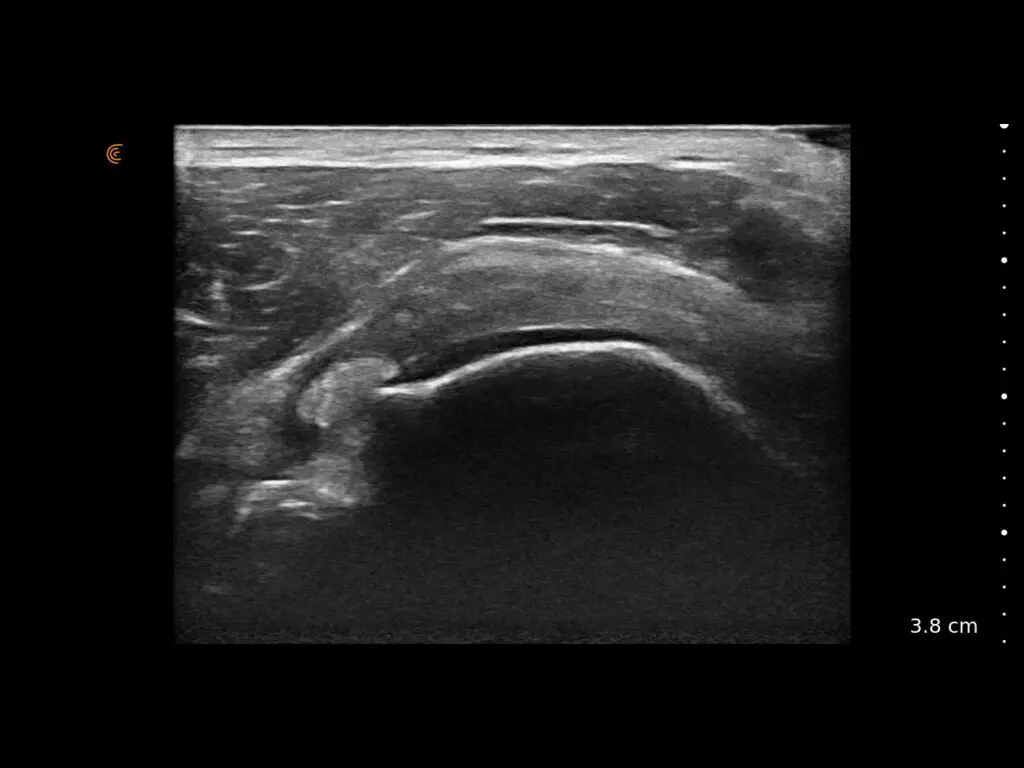

ProbeFix Dynamic is a new device that enables high-quality ultrasound measurements during dynamic exercise by keeping an ultrasound probe in place, allowing for muscle monitoring during intense movement and creating new research possibilities in muscle imaging.